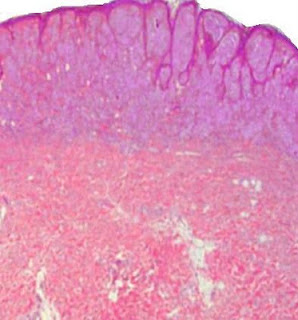

Image1 Image 2 Image3 Image4 Case 108 A 38 year old male with a nodule on the glans penis. Diagnosis

Acrodermatitis Chronica Atrophicans Visit: Dermatopathology Site Visit: Pathology of Acrodermatitis Chronica Atrophicans There is superficial and deep chronic inflammatory cellular infiltrate in the dermis. It is moderately heavy and composed mainly of lymphocytes together with histiocytes and plasma cells. There is telangiectasia and the cellular infiltrate is prominent around the blood vessels. Inflammatory cells are also present around the adnexae. Thickened collagen bundles are haphazardly present in the upper half of the dermis. There is some atrophy of the dermis and of the subcutis. The epidermis also shows variable atrophy with loss of rete pegs.

Image1 Image2 Image3 Image4 Image5 Case 102 A 68 year old male with ill-defined erythema on the extensor surface of the lower end of the right leg extending to the dorsum of the foot.There is associated wrinkling of the skin. Diagnosis